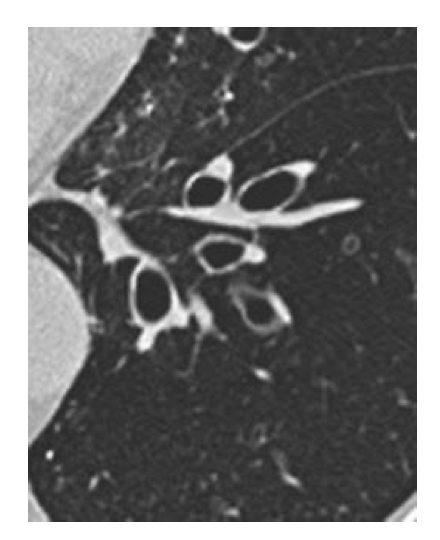

Classic CT finding of bronchiectasis

signet ring sign